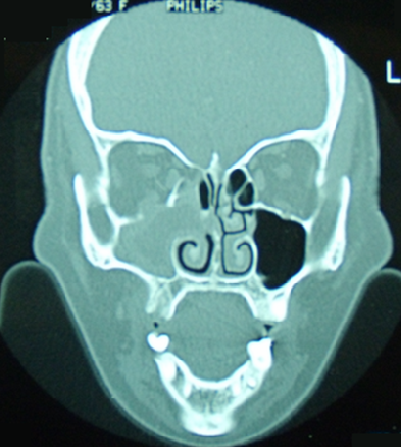

Le fibrosarcome naso-sinusien est une tumeur maligne rare. Il se manifeste le plus souvent par une obstruction nasale et une épistaxis ou une cacosmie. Seuls les examens anatomo-pathologiques et immuno-histochimique permettent de confirmer le diagnostic. Le pronostic est péjoratif en cas de retard diagnostique. Patient âgé de 52 ans a consulté pour une obstruction nasale droite, une épistaxis récidivante et une altération de l'état général évoluant depuis deux mois et une douleur orbitaire. L'examen biologique a trouvé un discret syndrome inflammatoire et une anémie hypochrome microcytaire ferriprive avec hémoglobine à 10,5 g/dl. La TDM du massif facial a révélé une tumeur comblant le sinus maxillaire droit, d'aspect isodense avec rehaussement en cadre du sinus après injection du produit de contraste. Il a aussi objectivé une lyse de la paroi médiale du sinus maxillaire droit, du cornet moyen, du plancher orbitaire et de la lame papyracée avec extension du processus en extraconal. Plusieurs diagnostics ont été suspectés en particuliers un lymphome, une néoplasie ou une aspergillose. Il a bénéficié d'une exérèse totale de la tumeur à la fois par voie endoscopique et chirurgicale. Les examens anatomo-pathologiques et immuno-histochimique ont confirmé le diagnostic de fibrosarcome naso-sinusien. Le bilan d'extension était négatif. Le traitement a été complété par une radiothérapie adjuvante. L'évolution était marquée par l'absence de récidive ou de métastase avec un recul d'un an.